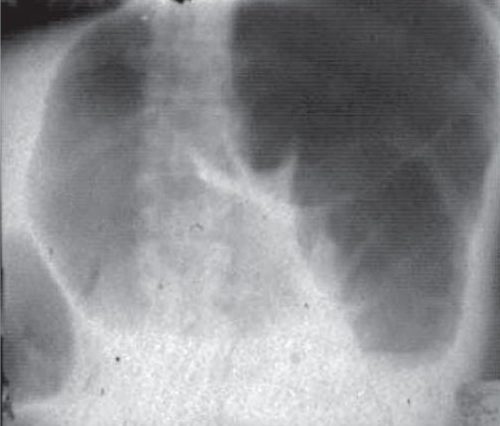

Диагноз устанавливается на основе анамнеза, результатов физикального обследования и инструментальных методов диагностики. Наиболее информативным из них является рентгенологическое исследование.

- Завернутая сигмовидная кишка на рентгеновском снимке выглядит как огромная шпилька, занимающая почти всю брюшную полость, внутри которой видны уровни жидкости.